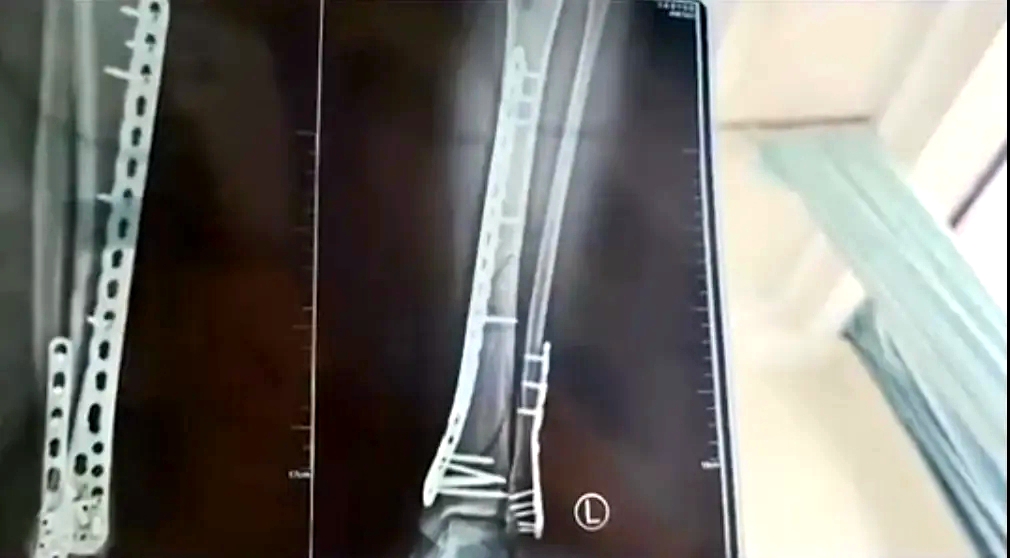

致左腿粉碎性骨折

近日,甘肅蘭州的武女士稱母親節(jié)當天,自己穿7cm厚洞洞鞋下樓,不慎崴腳摔倒,致使左腿粉碎性骨折。

武女士稱:因為洞洞鞋的鞋底比較厚,腳掌中間又是凹進去的,自己下樓梯的時候,正好踩到凹進去的地方,當時腳沒有踩穩(wěn),整個人的重心往前撲,所有重力都集中在腿上,結(jié)果就骨折了。

該女子稱,目前已做完手術(shù)在家休養(yǎng),不過下地得拄拐才行,且下地有時間限制,不能久站,而骨折完全康復(fù)可能需要3個月,她提醒大家穿增高鞋要注意。